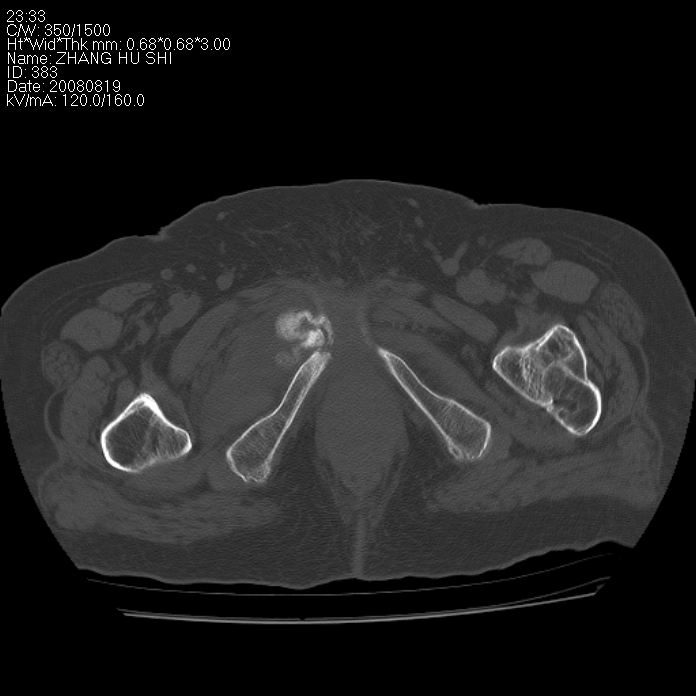

标题: CT15287:女 93岁 右髋关节疼痛 原左侧粗隆间骨折 CT发现右耻 [打印本页]

标题: CT15287:女 93岁 右髋关节疼痛 原左侧粗隆间骨折 CT发现右耻

支持转移并周围软组织侵犯右闭孔内肌侵犯,但tb不能完全除外。

耻骨软骨肉瘤可能性大